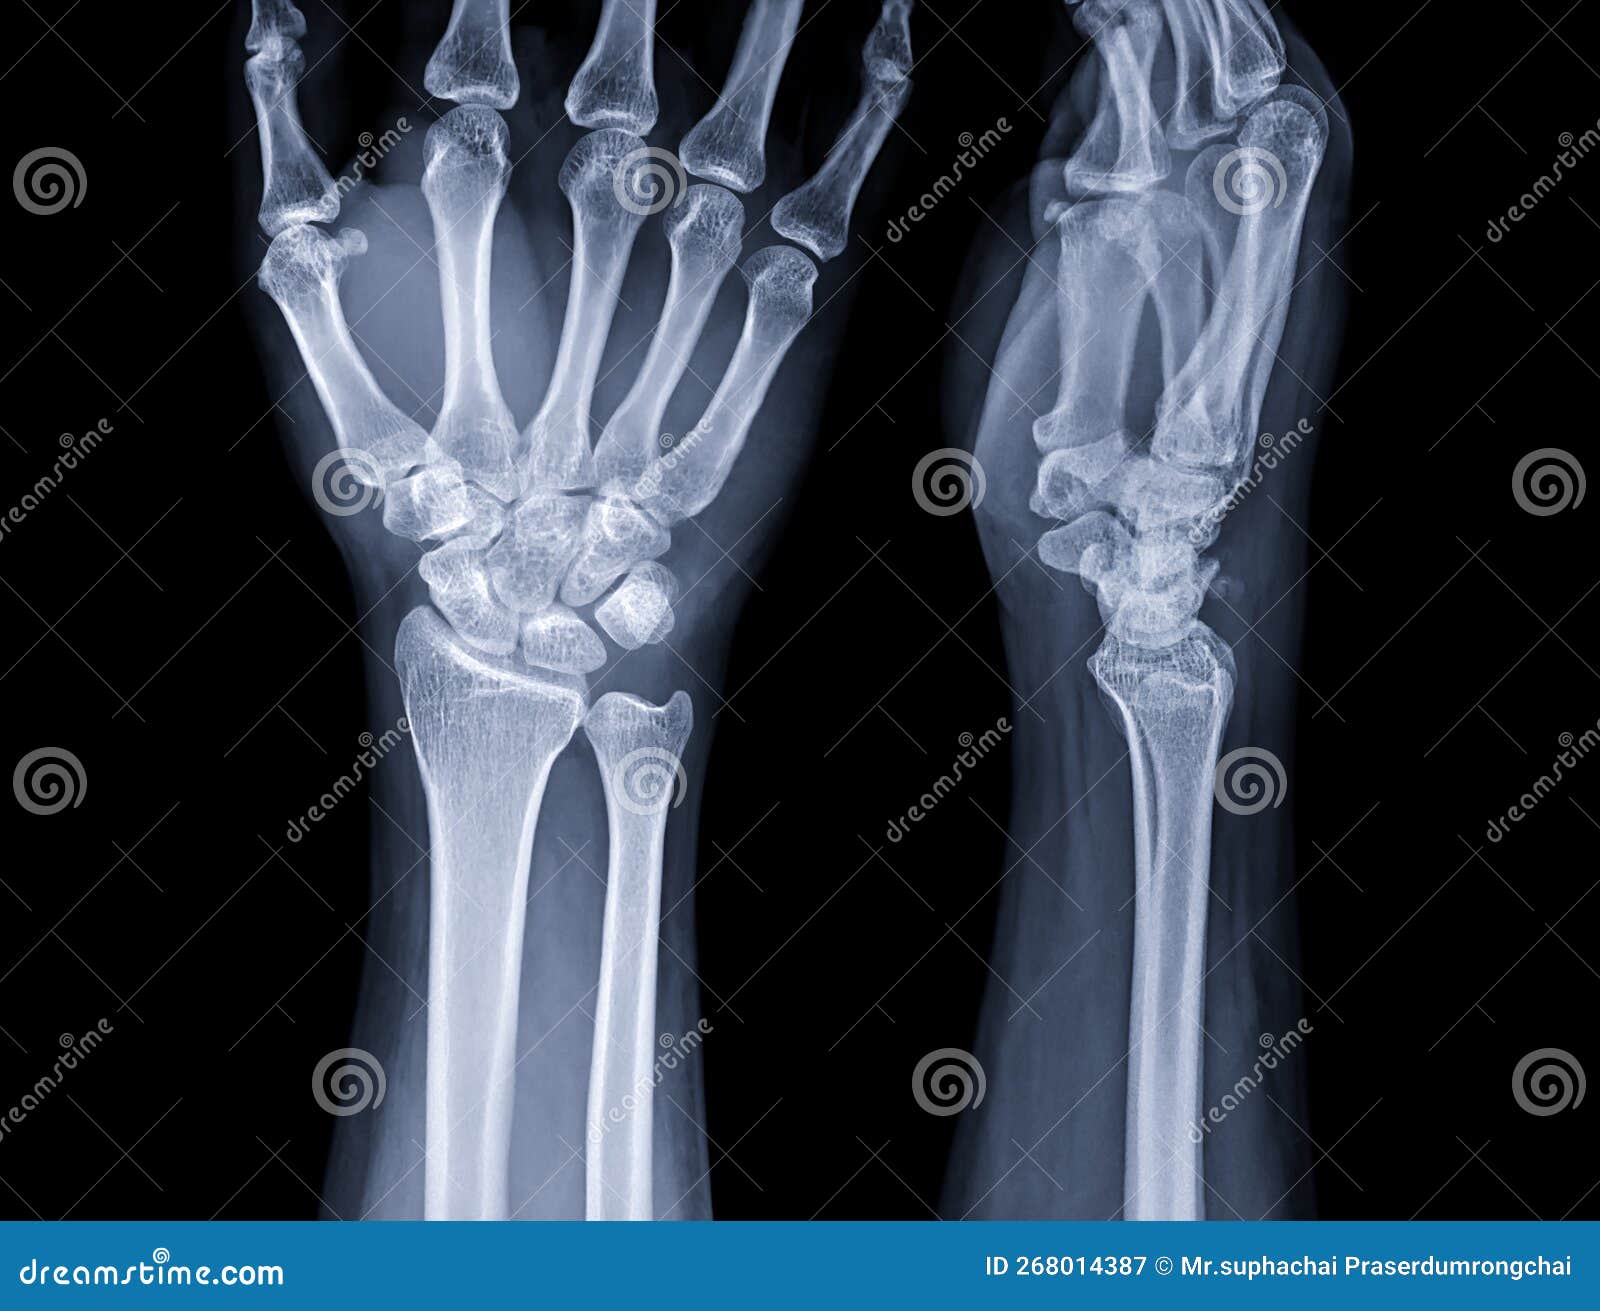

Given the complexity of the anatomy of the hand wrist, it is prone to various injuries, including fractures of the scaphoid bone, ligament tears, and nerve entrapments. Prevention strategies often center on strengthening the supporting muscles and ensuring that repetitive motions are punctuated by adequate rest periods. In cases of injury, recovery often involves immobilization or physical therapy designed to retrain the intrinsic muscles of the hand and restore the natural glide of the tendons through their sheaths.

Clinical assessments of the wrist often involve testing for specific signs of inflammation or nerve compression. By monitoring grip strength and range of motion, therapists can determine if the underlying structures are healing correctly. It is always best to consult with a medical professional if you experience persistent tingling, numbness, or weakness in the hand, as these are often indicators that the nerve pathways are under pressure.